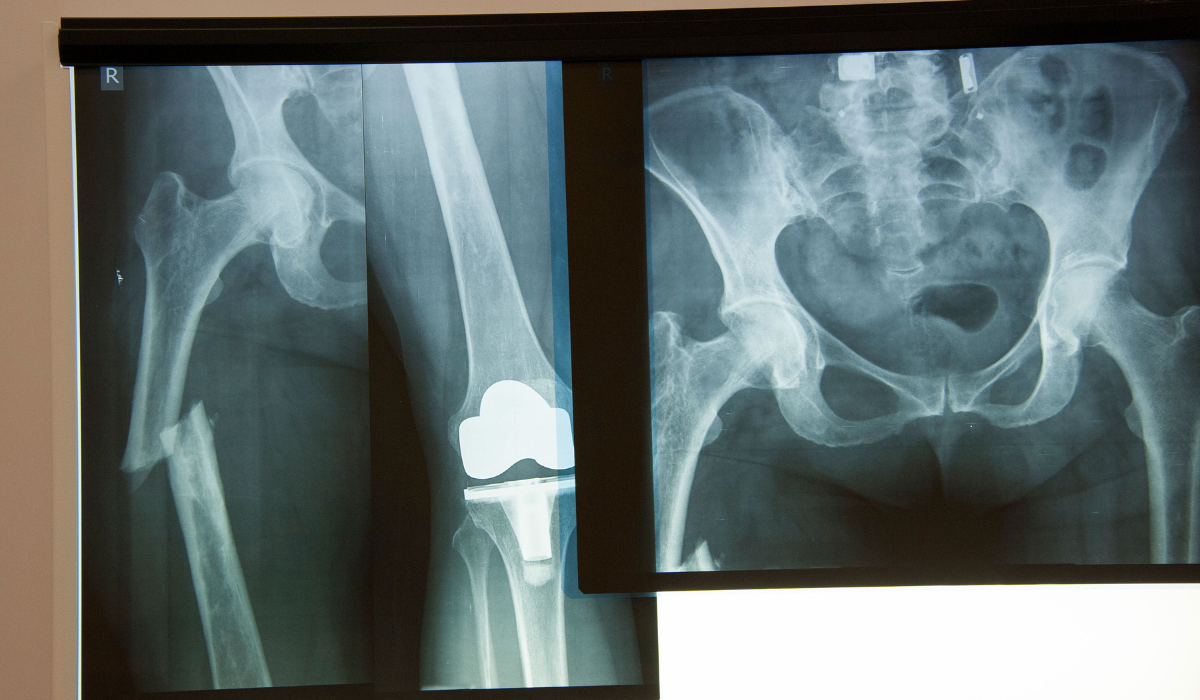

We offer comprehensive care for hip fractures—from diagnosis to surgery and post-operative rehabilitation. The process begins with clinical assessment, X-rays, and sometimes CT scans to evaluate the fracture type. Based on the findings, our orthopedic team develops a tailored surgical plan. Internal fixation is preferred for non-displaced or stable fractures, using metal screws, rods, or plates to hold the bone together.

For displaced or severe fractures—especially in older adults—partial or total hip replacement is recommended. In hemiarthroplasty, the femoral head is replaced with a prosthesis, while in total hip replacement, both the femoral head and hip socket are replaced. These procedures are performed under spinal or general anesthesia with precision and care.